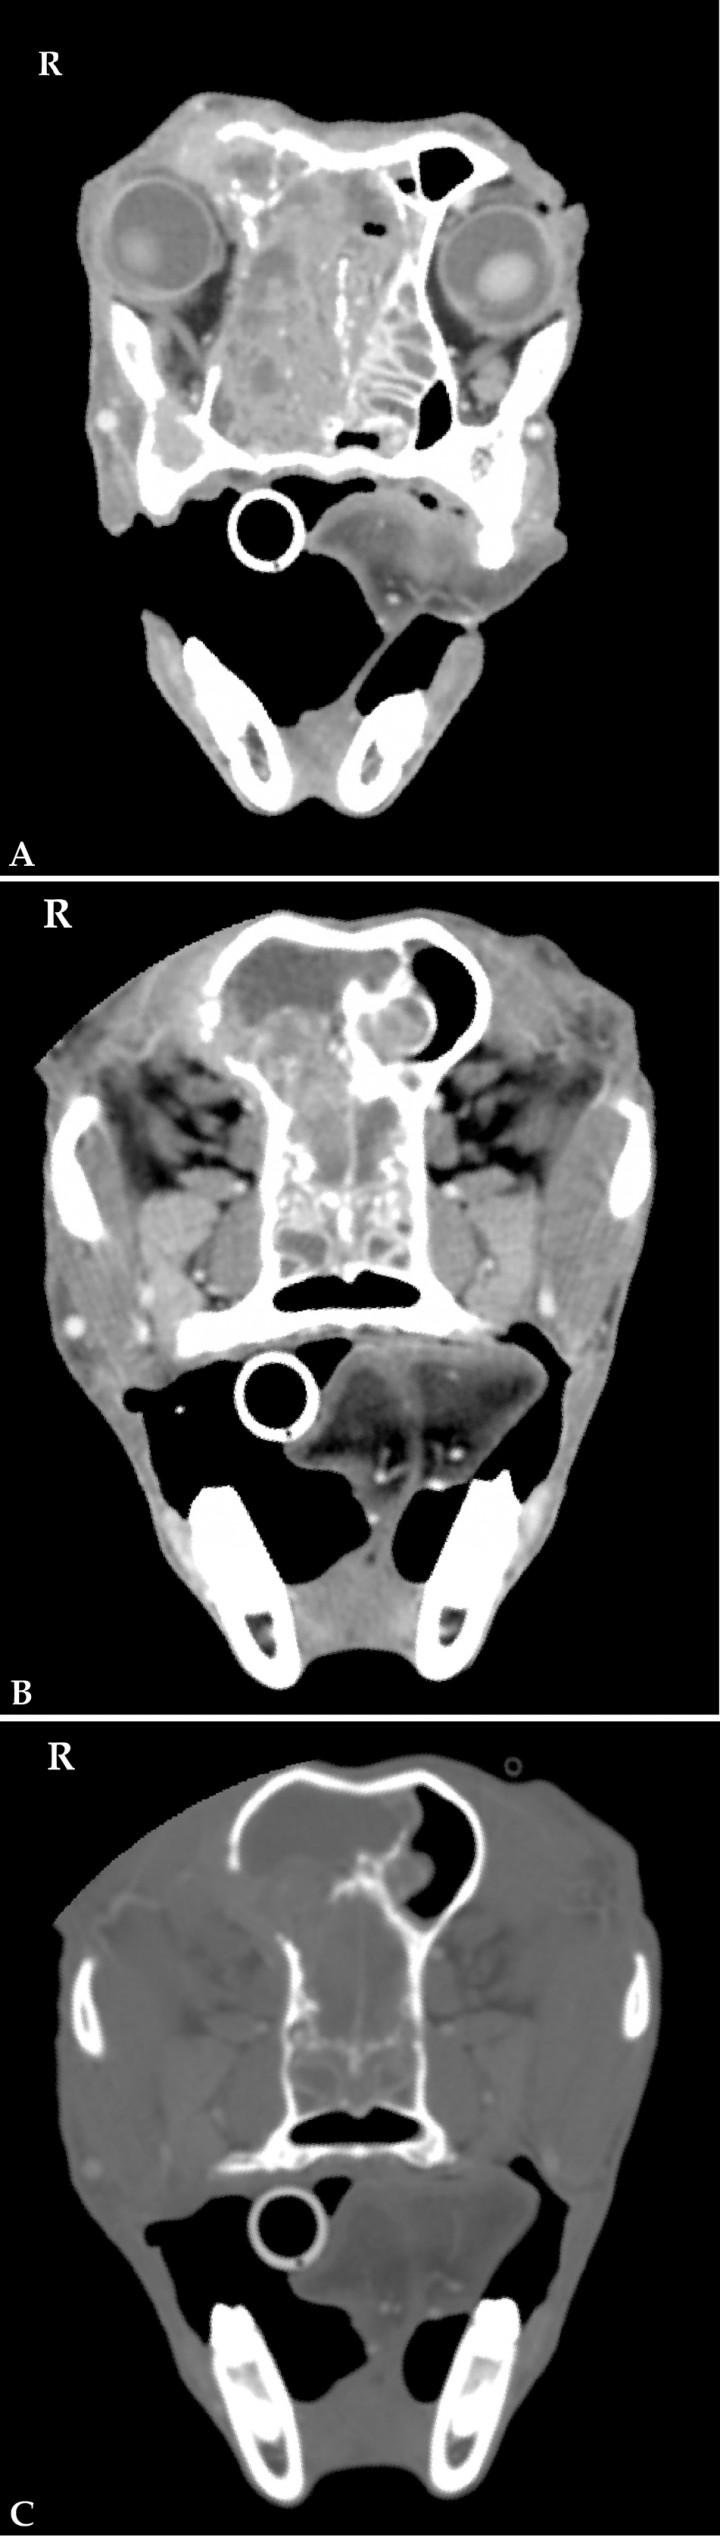

One main indication for CT is the assessment of nasal tumours. In cats lymphoma is the most common nasal neoplasia,[ Nemanic S, Hollars K, Nelson NC et al.: Combination of computed tomographic imaging characterisitics of medial retropharyngeal lymph nodes and nasal passages aids discrimination between rhinitis and neoplasia in cats. Vet Radiol Ultrasound 2015; 56:617-627. [PubMed] , Tromblee TC, Jones JC, Etue AE et al.: Association between clinical characteristics, computed tomography characteristics, and histologic diagnosis for cats with sinonasal disease. Vet Radiol Ultrasound 2006; 47:241-248. [Wiley] ] whereas in the dog carcinomas are most frequent.[ Avner A, Dobson JM, Sales JI et al.: Retrospective review of 50 canine nasal tumours evaluated by low-field magnetic resonance imaging. J Small Anim Pract 2008; 49:233-239. [PubMed] ] CT features associated with nasal neoplasia include soft tissue masses within the nasal cavity with heterogeneous contrast uptake, destruction of the turbinates, lysis of the adjacent bones and intracranial extension.[ Nemanic S, Hollars K, Nelson NC et al.: Combination of computed tomographic imaging characterisitics of medial retropharyngeal lymph nodes and nasal passages aids discrimination between rhinitis and neoplasia in cats. Vet Radiol Ultrasound 2015; 56:617-627. [PubMed] , Tromblee TC, Jones JC, Etue AE et al.: Association between clinical characteristics, computed tomography characteristics, and histologic diagnosis for cats with sinonasal disease. Vet Radiol Ultrasound 2006; 47:241-248. [Wiley] ] CT is the modality of choice in displaying bone changes, which showed to best assess lysis of the turbinates and cribiforme plate (Fig 1).[ Drees D, Forrest LJ, Chappell R: Comarison of computed tomography and magnetic resonance imaging for the evaluation of canine intranasal neoplasia. J Small Anim Pract 2009; 50:334-340. [PubMed] ] Nevertheless, a recent study showed that CT and magnetic resonance imaging (MRI) had a high level of agreement concerning bone involvement of nasal cavity and head. In addition, MRI showed a higher likelihood of identifying meningeal enhancement, which can be due to tumoral extension, peritumoral meningitis or oedema. MRI has a better soft tissue detail, however it is less available, more expensive and CT might be needed anyhow for radiation therapy planning.[ Lux CN, Culp WTN, Johnson LR et al.: Prospective comparison of tumor staging using computed tomography versus magnetic resonance imaging findings in dogs with nasal neoplasia: A pilot study. Vet Radiol Ultrasound 2017; 58:315-325. [PubMed] ]

<div>

<div class=\"Basic-Text-Frame\">

<p>Nasal carcinoma in a 12 year-old German Shepherd. (A) CT transverse image in soft tissue window at the level of the retrobulbar space. There is a large, heterogeneous, contrast-enhancing mass mainly located in the right nasal cavity. Note the severe destruction of the nasal and ethmoid turbinates and frontal bone and nasal septum, with extension of the mass into the left nasal cavity. (B) CT transverse image in soft tissue and (C) bone windows at the level of the frontal sinus. Focal destruction of the right dorsolateral aspect of the cribiforme plate and right frontal bone and protrusion of the mass into the calvarium and the right frontal sinus. R: right.</p>

Figura 1

Nasal carcinoma in a 12 year-old German Shepherd. (A) CT transverse image in soft tissue window at the level of the retrobulbar space. There is a large, heterogeneous, contrast-enhancing mass mainly located in the right nasal cavity. Note the severe destruction of the nasal and ethmoid turbinates and frontal bone and nasal septum, with extension of the mass into the left nasal cavity. (B) CT transverse image in soft tissue and (C) bone windows at the level of the frontal sinus. Focal destruction of the right dorsolateral aspect of the cribiforme plate and right frontal bone and protrusion of the mass into the calvarium and the right frontal sinus. R: right.